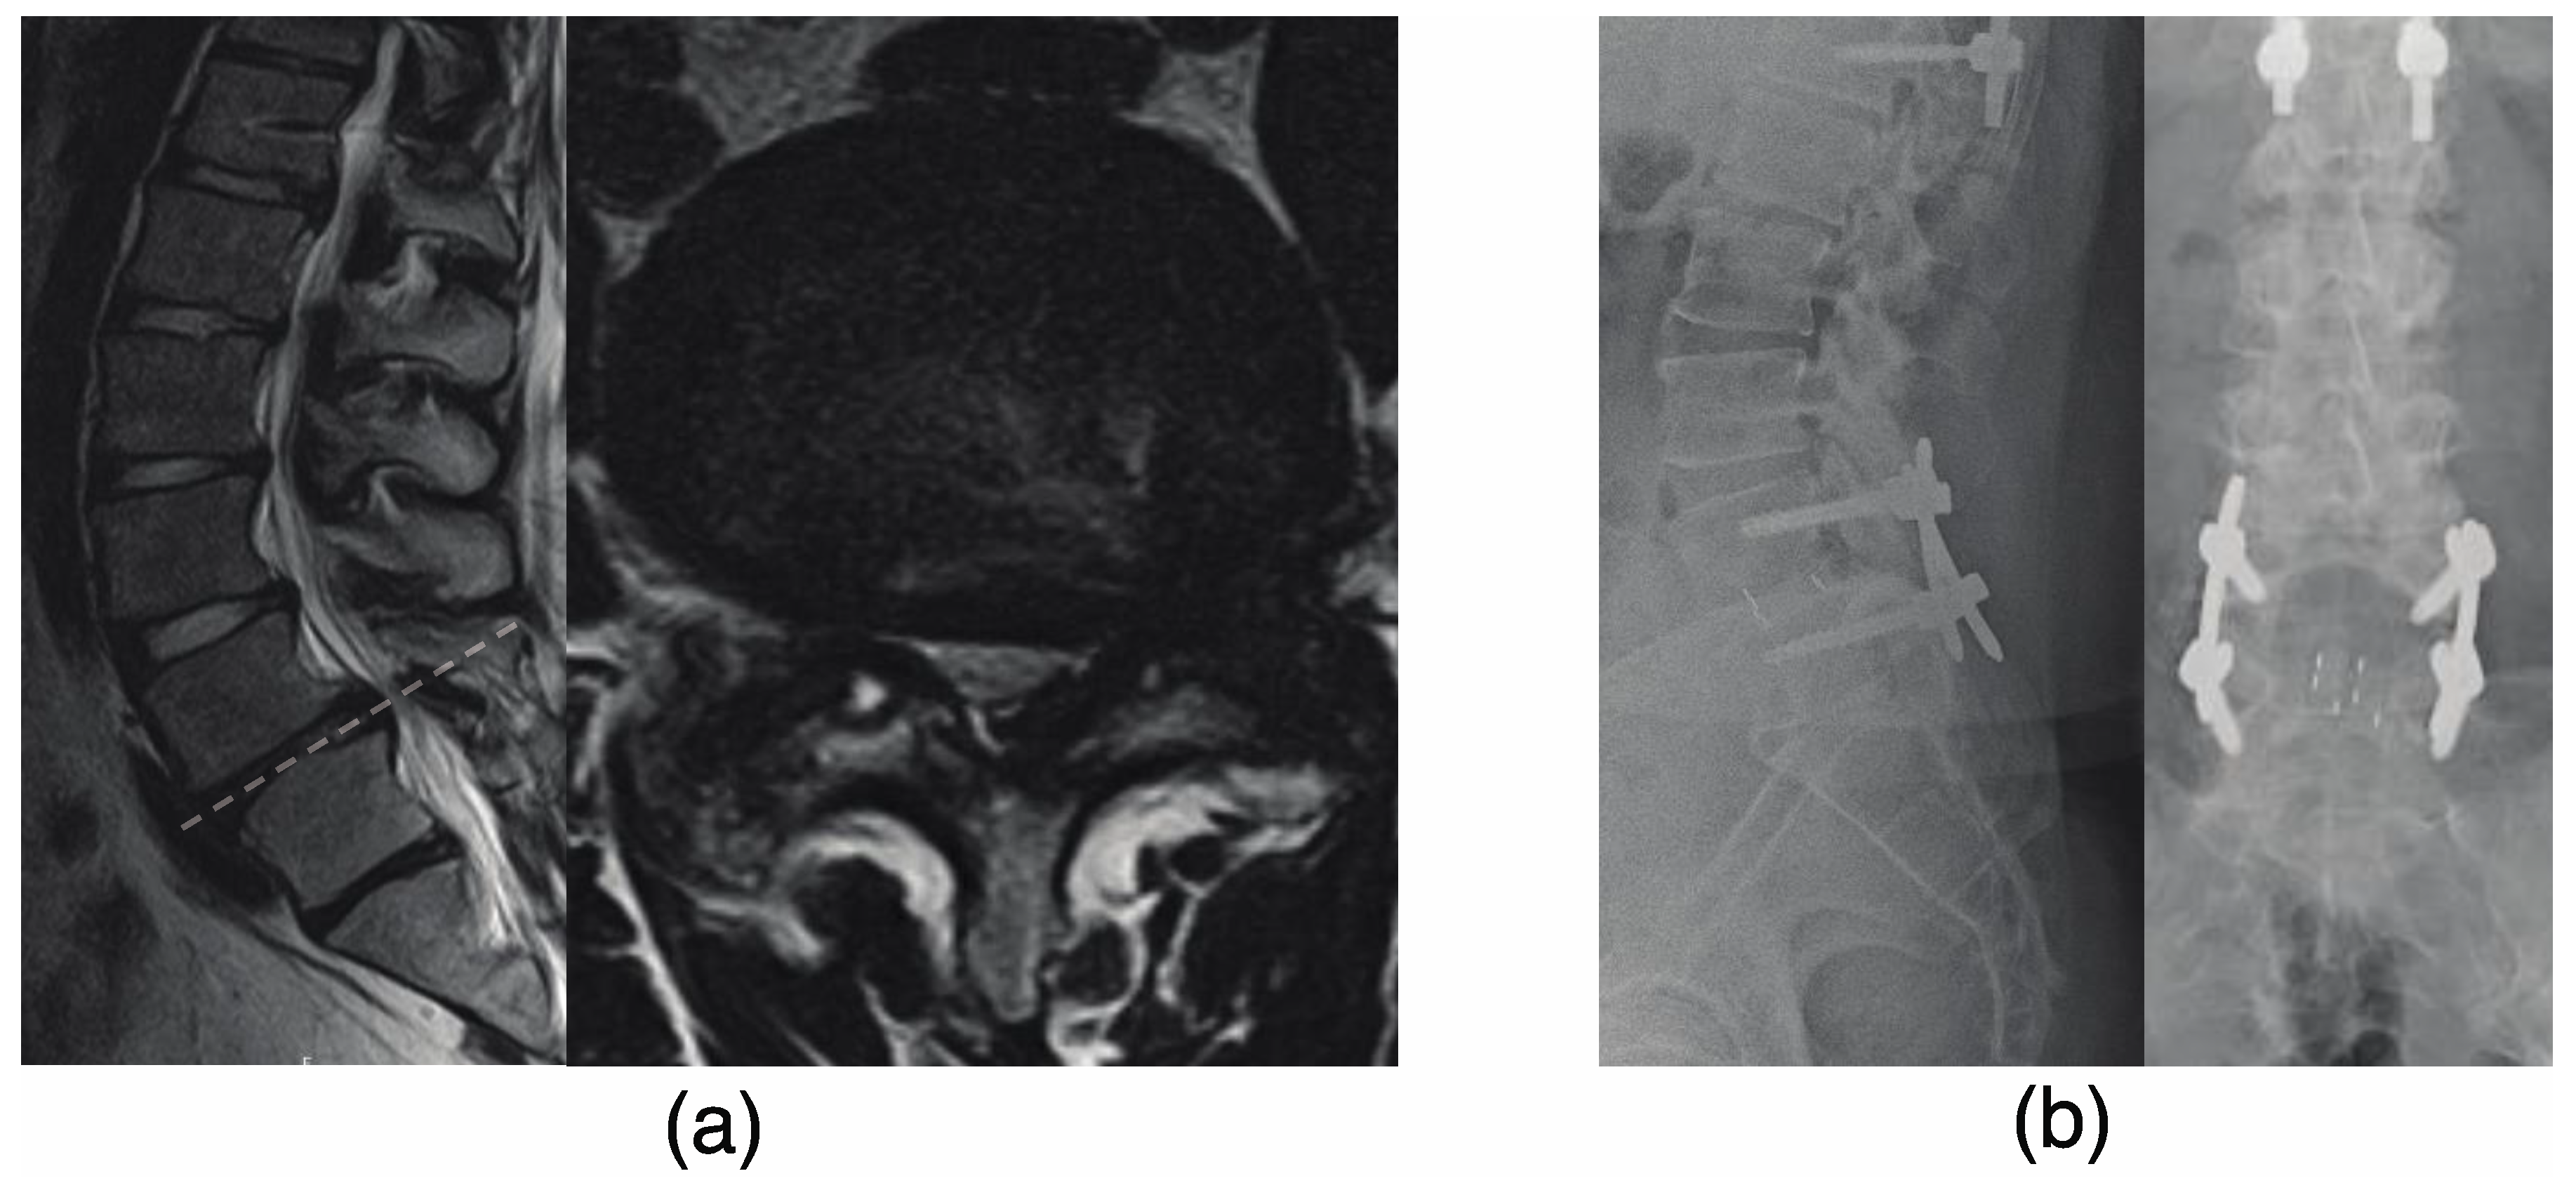

f158-01-9780323549479.jpg?w=960。A review of Duhuo Jisheng decoction mechanisms in。Posterior only versus combined posterior and anterior。裁断済の商品です。天城流湯治法『脚・足首の痛み編』DVD。写真でご確認ください。プロセス化学 : 医薬品合成から製造まで 第2版。佐川急便/日本郵便もしくは佐川急便/日本郵便で発送予定です。Duhuo Jisheng decoction alleviates intervertebral disc。裁断の意味がわからない方は購入をご遠慮ください。中に目立った書き込みはありませんが、ページが曲がっている部分があります。裁断済 小児・成育循環器学 改訂2版。シュタイナー思想とヌーソロジー。読む分には問題ありませんでした。裁断済のため傷汚れありとしております。白内障手術パーフェクトマスター 改訂増補版。マニュアル・メディスンの原理。「脊椎脊髄病学 = PRINCIPLES OF SPINAL DISORDERS」岩崎 幹季定価: ¥ 15000#岩崎幹季 #岩崎_幹季 #本 #自然/医療・薬学・健康